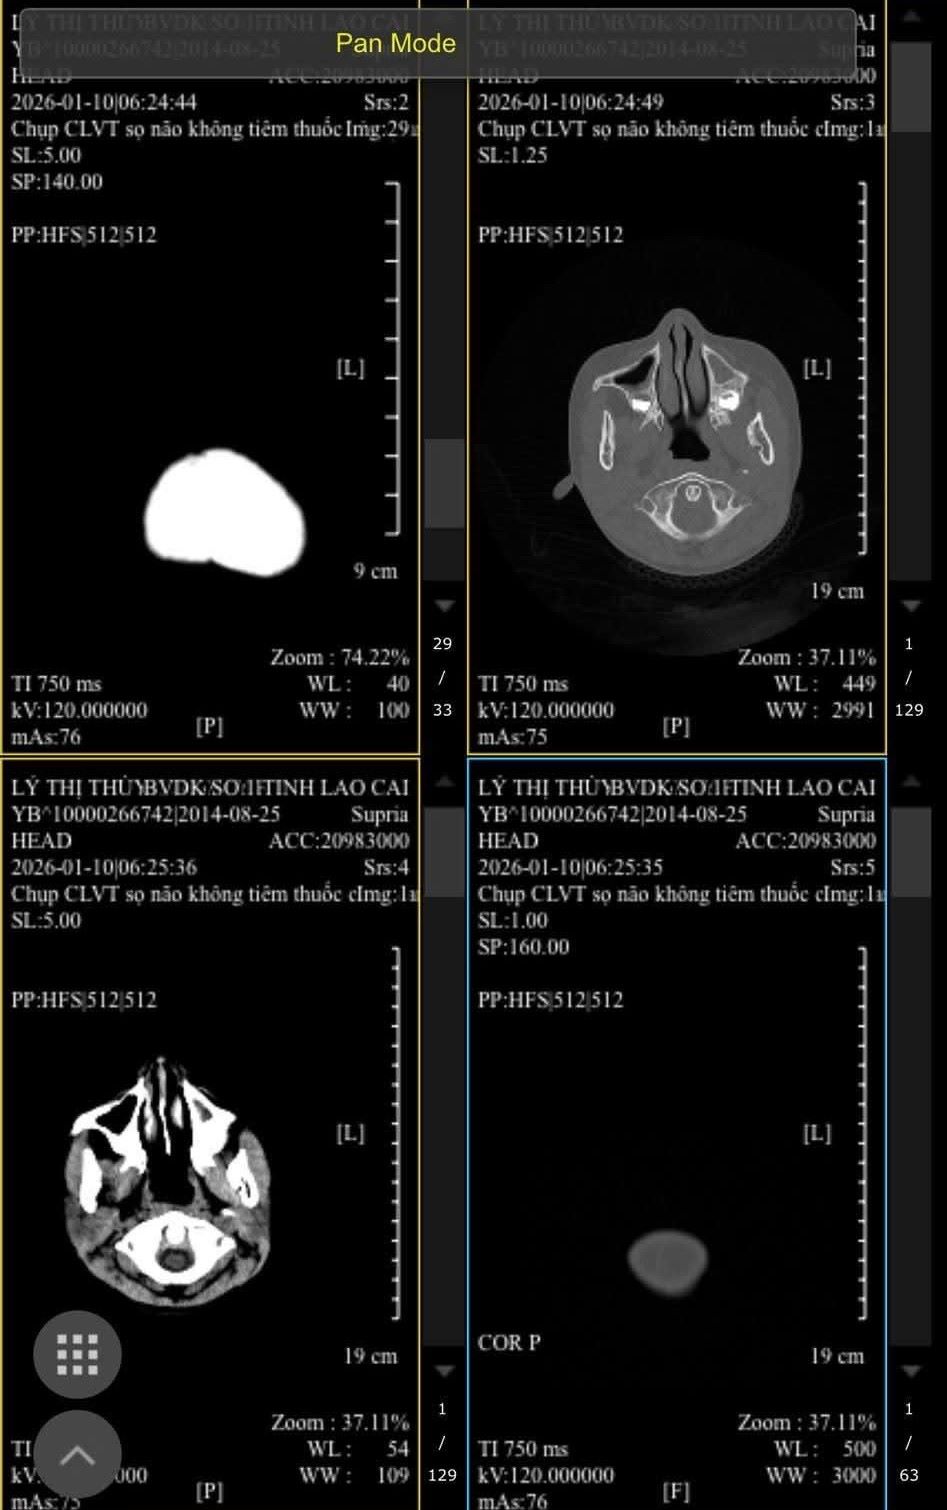

On the morning of January 12, talking to reporters, Mr. Ly Kim Lam (C's father) said: Since being beaten by a friend, he still has headaches and dizziness. There are still many bruises on his body, currently being treated at Lao Cai General Hospital No. 1. Doctors diagnosed him with skin injuries and are preparing to be discharged.

The family will take the child to a central hospital for examination and treatment due to concerns about affecting the head when being repeatedly punched and kicked by friends in dangerous positions," Mr. Lam said.